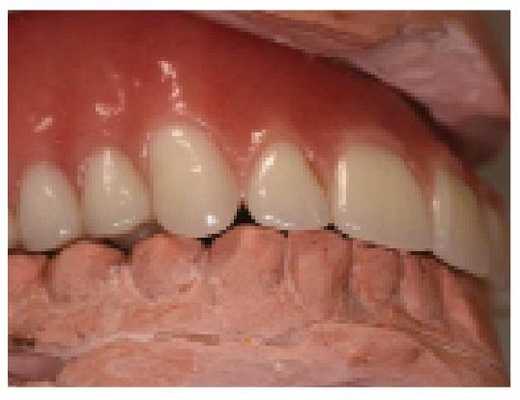

Реабилитация пациентов с полной адентией является непростой клинической задачей. Однако при реализации вышеописанного систематического подхода врачу удается добиться надлежащего восстановления функции, эстетики и фонетики в результате проведенного лечения (фото 12).

Фото 12. Вид окончательных конструкций полных съемных протезов в ротовой полости.